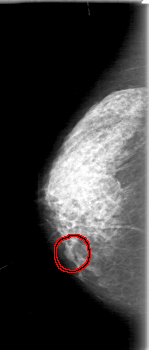

FILE: D_4079_1.RIGHT_MLO.OVERLAY

TOTAL_ABNORMALITIES 1

ABNORMALITY 1

LESION_TYPE MASS SHAPE LOBULATED MARGINS OBSCURED

ASSESSMENT 0

SUBTLETY 3

PATHOLOGY BENIGN

TOTAL_OUTLINES 1

FILE: D_4079_1.RIGHT_CC.OVERLAY